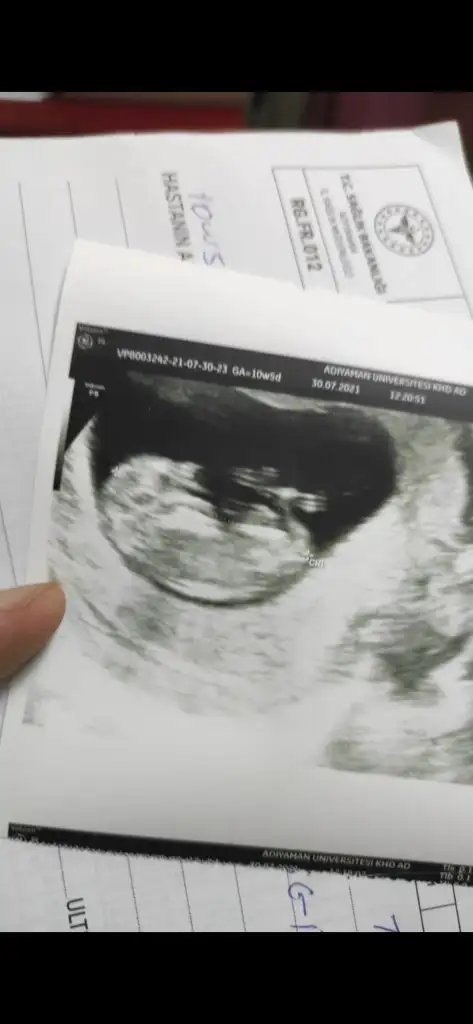

Burada 9+4 üz tahmin alabilir miyiz karından ultrason merak işte teşekkürler şimdidenErkek görünüyor![]()

Çok erken en iyi 11 12 13 haftalar olmalı şimdilik kız yönünde ama yanıltabilirBurada 9+4 üz tahmin alabilir miyiz karından ultrason merak işte teşekkürler şimdidenEki Görüntüle 2894467